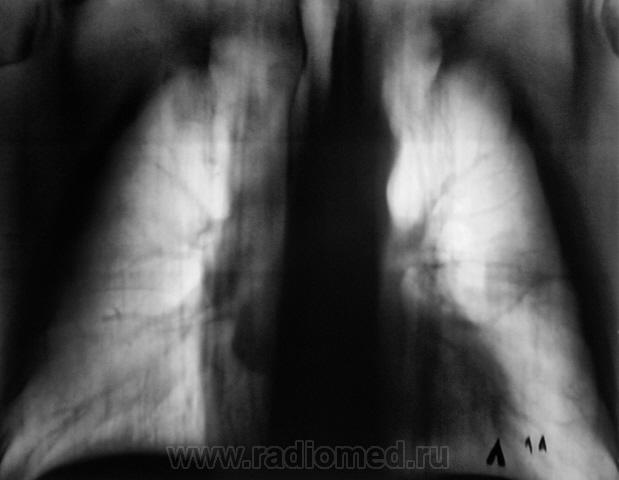

В апреле 2009 года пациент пришел "для динамического наблюдения" - серия 2.

После повторного дообследования (апрель 2009 г) - 2 серия изображений, мы были твердо уверены, что пациент взят на учет..., но не тут-то было. В пятницу рентгенолаборант флюорографа попросил подойти и "глянуть снимок"...

Оказывается "данный" пациент направлен для прохождения профилактической флюорографии..., так как надо было поменять водительские права...?

Вот флюорограммы.

2. Конечно, мы на свой страх и риск, произвели дообследование, согласно стандарту. Итог дообследования представлен в серии 3.

Было сказано, что "У Вас ничего нет, Вам просто надо бросить курить". НА УЧЕТ ПАЦИЕНТ НЕ ПОСТАВЛЕН, ДИАГНОЗ ТАКЖЕ НЕ ПОСТАВЛЕН.

Все признаки периферического рака...."расти" так может и лет пять...пока репу в диспансере будут чесать...

В заключении, именно однозначно, выставлен данный диагноз, изображения и все необходимое записано на диск. Это не ошибка для ООД. В ООД такой ошибки быть не может, ибо это специализированное учреждение.  Кстати, это, как Вы понимаете, случай не единичный.